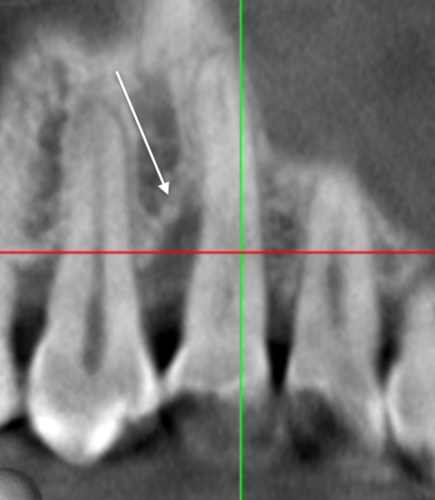

レントゲン的にも骨がないことが確認できます

しかし、ここに再生療法を行うと・・・

黒いところが、白くなっている、つまり骨が出来た、再生したということです